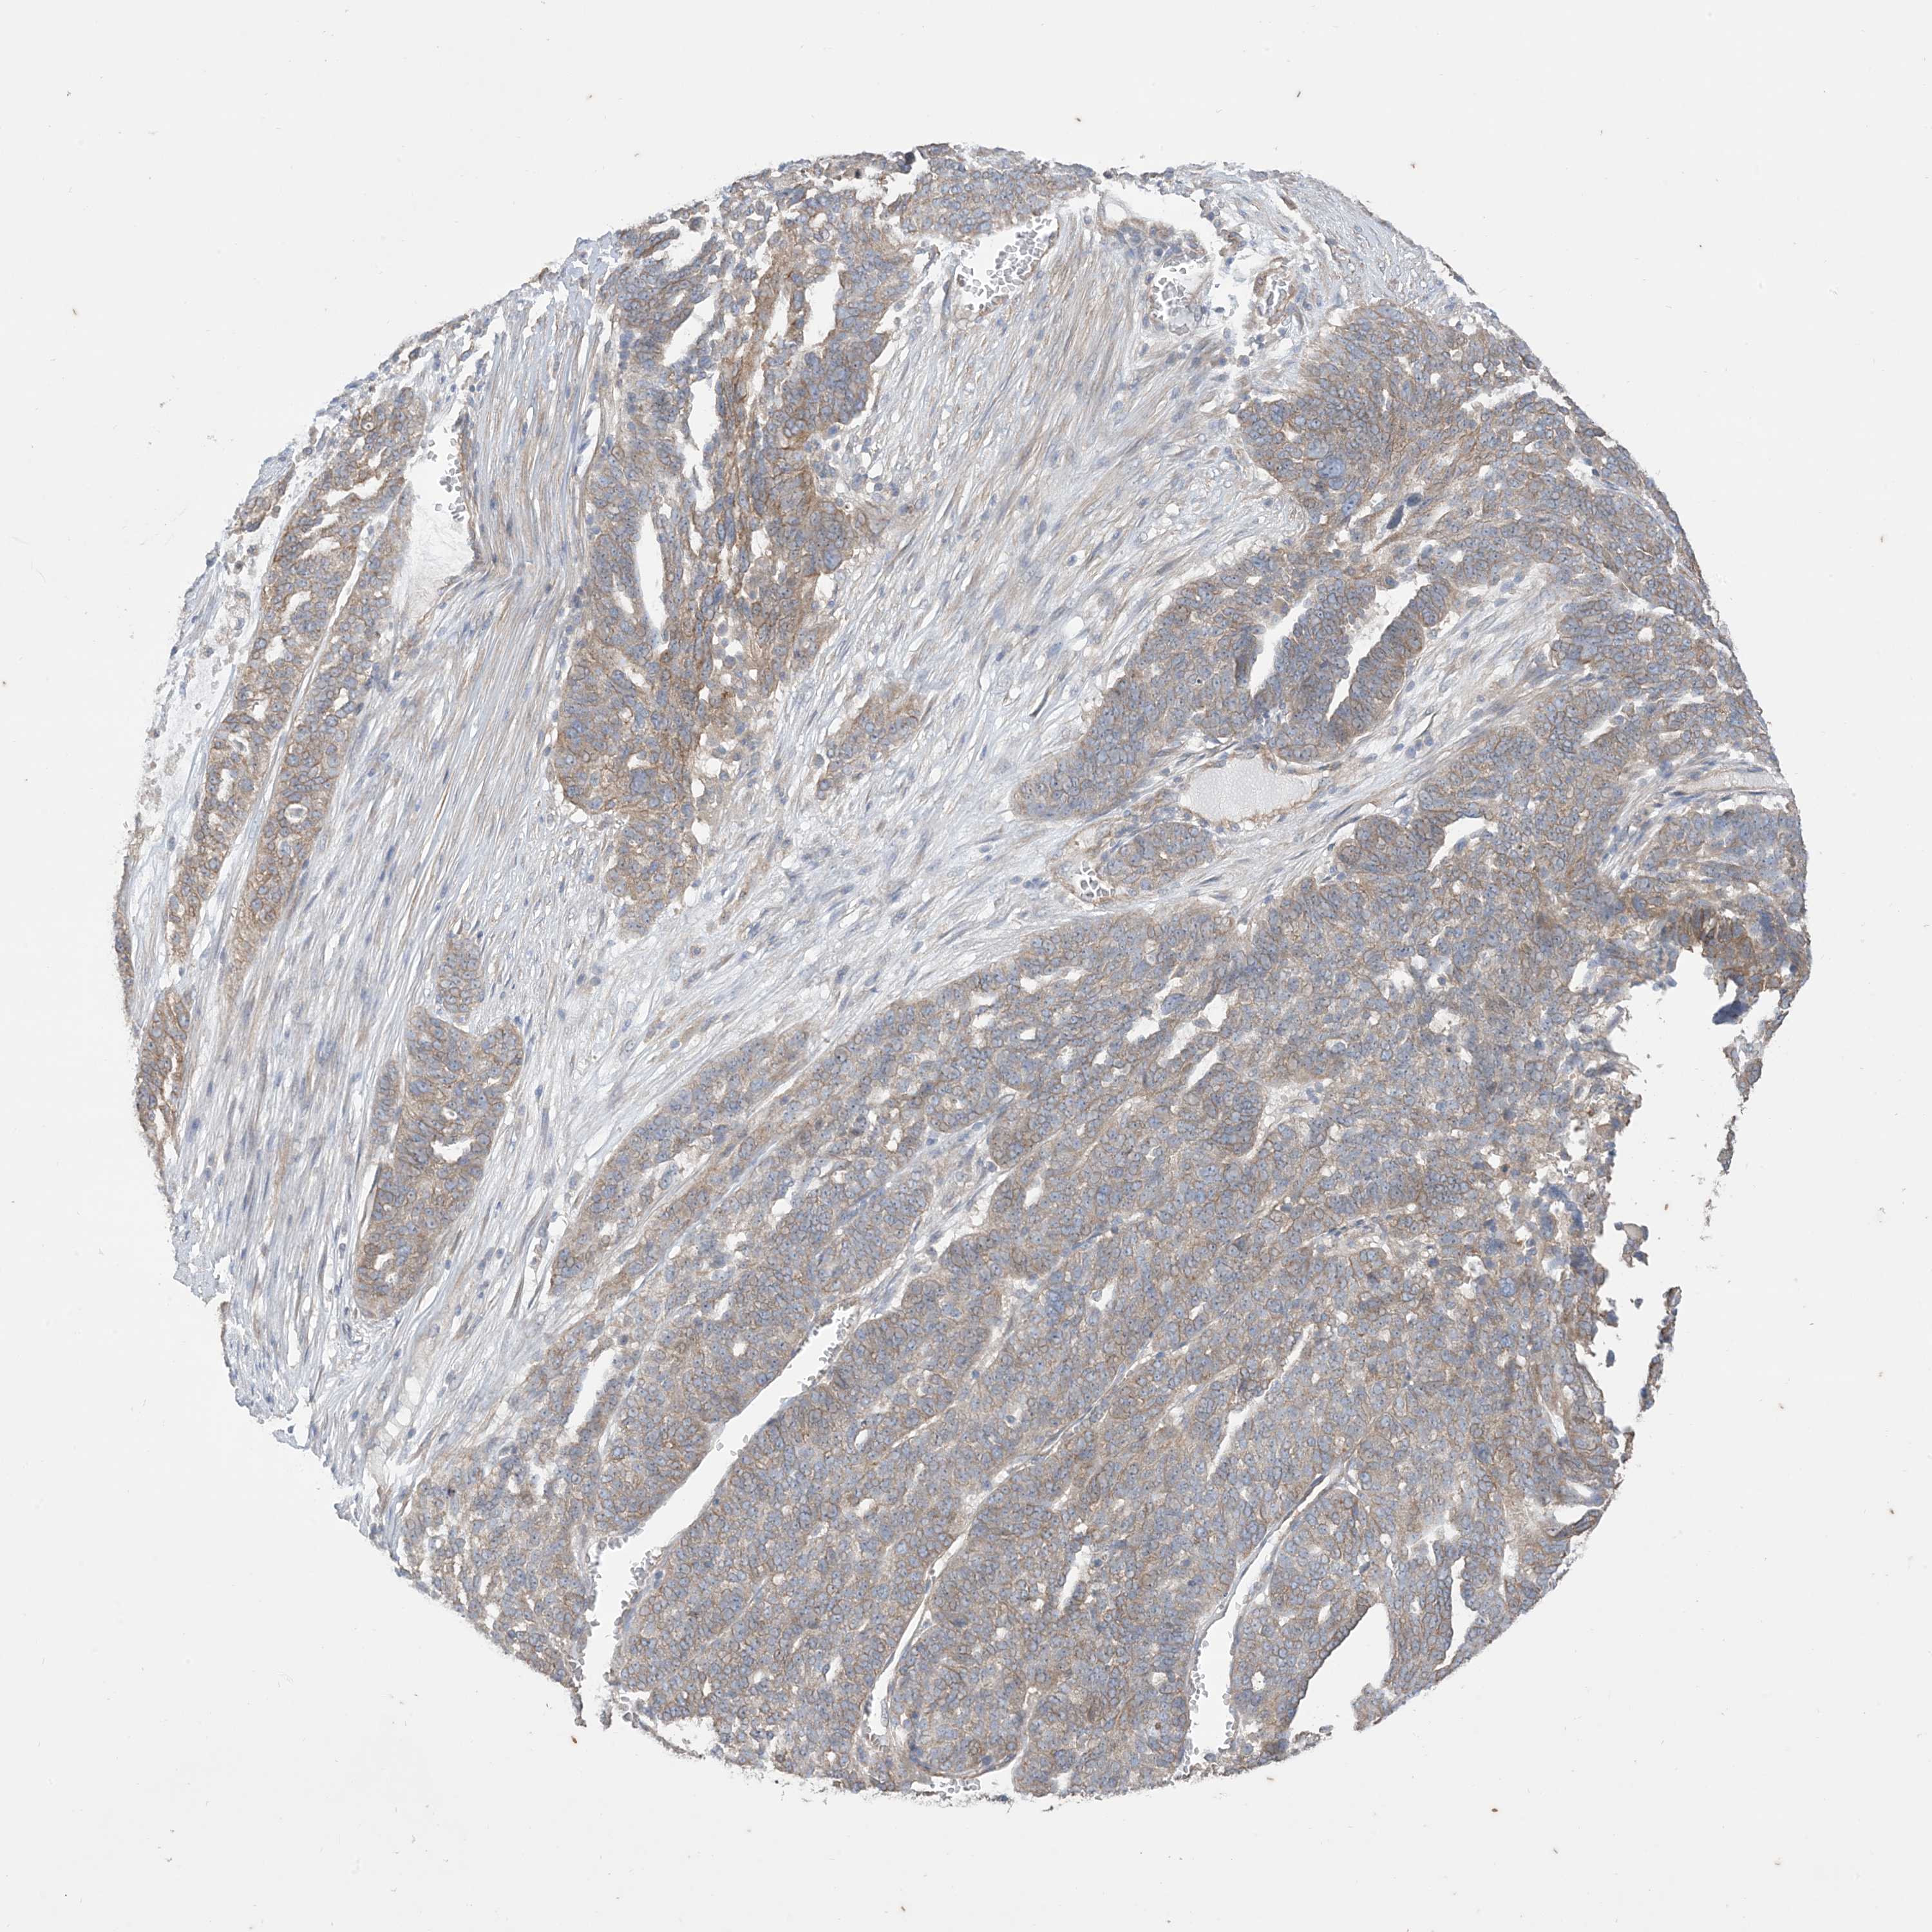

OVARIAN CANCER - Protein expressioni

A mouse-over function shows sample information and annotation data. Click on an image to view it in a full screen mode. Samples can be filtered based on level of antibody staining by selecting one or several of the following categories: high, medium, low and not detected. The assay and annotation is described here.

Note that samples used for immunohistochemistry by the Human Protein Atlas do not correspond to samples in the TCGA dataset.

Antibody stainingi

Antibody staining in the annotated cell types in the current human tissue is reported as not detected, low, medium, or high, based on conventional immunohistochemistry profiling in selected tissues. This score is based on the combination of the staining intensity and fraction of stained cells.

Each image is clickable and will lead to virtual microscopy that enables deeper exploration of all samples and also displays staining intensity scores, fraction scores and subcellular localization as well as patient and tissue information for each sample.

Antibody HPA036290

Staining

High

Medium

Low

Not detected

Intensity

Strong

Moderate

Weak

Negative

Quantity

>75%

75%-25%

<25%

None

Location

Nuclear

Cytoplasmic/membranous

Cytoplasmic/membranous,nuclear

Cystadenocarcinoma, serous, NOS

Carcinoma, endometroid

Cystadenocarcinoma, mucinous, NOS

Carcinoma, NOS